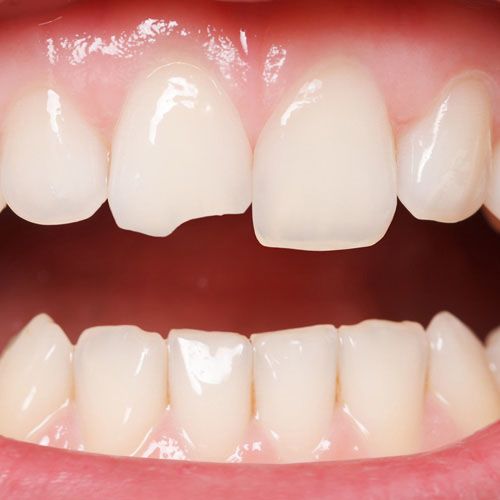

What it looks like:

You might only notice it when you run your tongue over the edge of your tooth or catch it in the mirror at the right angle. It doesn’t hurt and isn’t sensitive to hot or cold.

This is the most common type of chipped tooth we treat. You might feel sensitivity when you eat or notice a sharp edge where the break occurred.